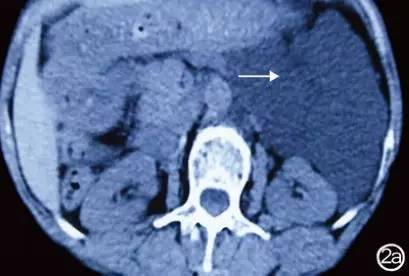

CT检查:胰腺体尾部后方囊性占位性病变;大小约8.0cm×12.0cm,紧邻左肾及腹主动脉,增强后囊壁无明显强化,其内分隔亦未见强化。见图2。

图2 CT检查结果 胰腺体尾部可见囊性占位性病变(→),紧邻左肾及腹主动脉,增强后动脉期及静脉期囊壁无明显强化,其内分隔亦未见强化 a:平扫;b:增强扫描;c:冠状位

血管淋巴管瘤超声检查结果表现为边界锐利的囊性占位性病变。本例患者B超检查发现囊性占位性病变内部为无回声区,边界清晰,内部呈多房性分隔。超声检查对此类肿瘤的诊断有参考价值,CT检查可进一步定性定位辅助诊断。CT表现为囊实性占位性病变,以囊性为多见,壁薄,囊腔大小不一,可表现为囊性低密度灶或等密度灶。增强时囊内部分无强化,实质部分及分隔动脉期轻度强化,静脉期及延迟期强化逐渐明显。血管淋巴管瘤内可见大量扩大的淋巴管和毛细血管,管腔内有淋巴液、少量淋巴细胞和红细胞,管壁间有淋巴细胞浸润。